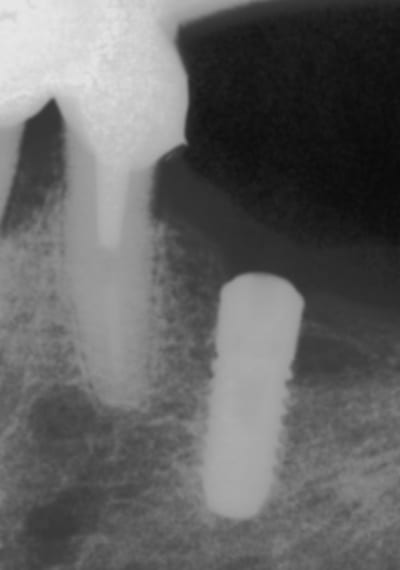

Cet aprem donc pose d'un Natea 3,6/10, l'équivalent de l'osseospeed ancienne version ( pas TX);par exemple sur ce cas pour le même prix j'aurais pu en poser deux ( mais pas de hauteur )

-agénesie patiente 18 ans

-osseospeed TX 3,5, pilier Atlantis Zircone et Procera

sans prétention aucune